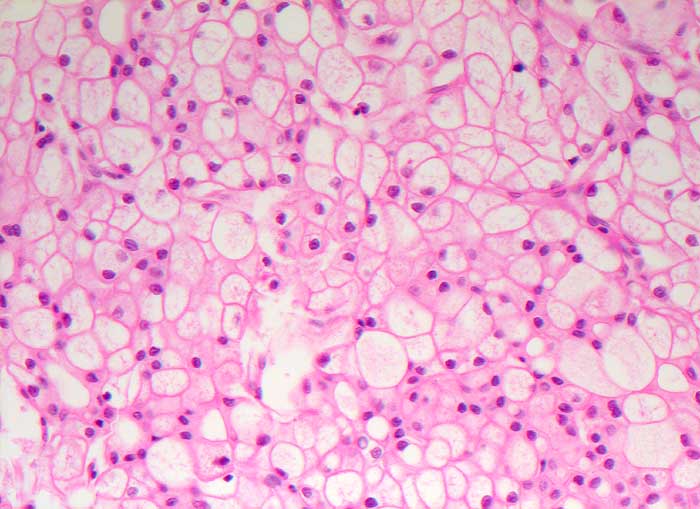

PathoPic – image database / PathoPic ID 6582 - Chromophobes Nierenzellkarzinom

Chromophobes Nierenzellkarzinom

maligner Tumor

Niere

Beschreibung

Histologie

200